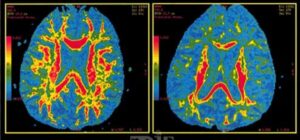

– MRI مبتنی بر هوش مصنوعی: در کنار نتایج ژنتیکی بهصورت ترکیبی برای ارزیابی خطر فردی بهکار میرود.